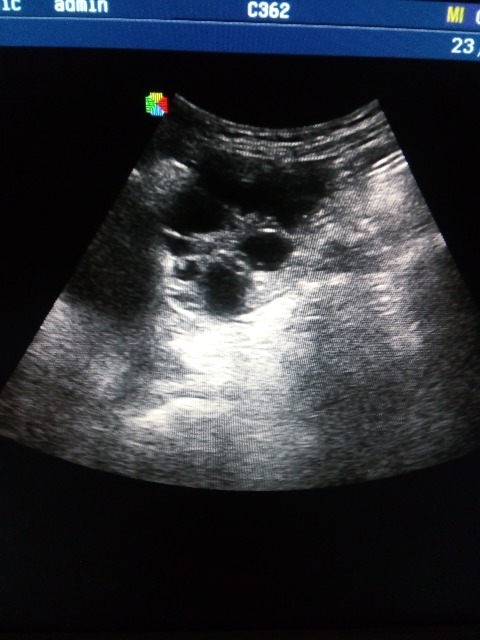

Подскажите что это может быть, лоцируется на уровне дна матки, справа и слева, больше слева, у женщины c-r шейки матки, проходит обследование брюшной полости перед лечением в онкодиспансере, недавно делали УЗИ малого таза, без патологии, никаких образований, кист не находили, жалоб нет. Думаю расширенные петли кишечника, заполненные жидким содержимым, перистальтики не увидела, если это они то какая может быть причина, и как то нужно это в протоколе и заключении отразить?

По фото можно подумать и про яичники и по некоторым фото про петли. Нужно видео!

Форма вытянутая, общей капсулы нет и с двух сторон, наверное кишечник, просто я его таким не видела еще.. ну а если абстрагироваться от этого случая, то что вообще писать в заключении в случае расширенных и заполненных жидкостью петель, если больной амбулаторный планово пришел? какие рекомендации?